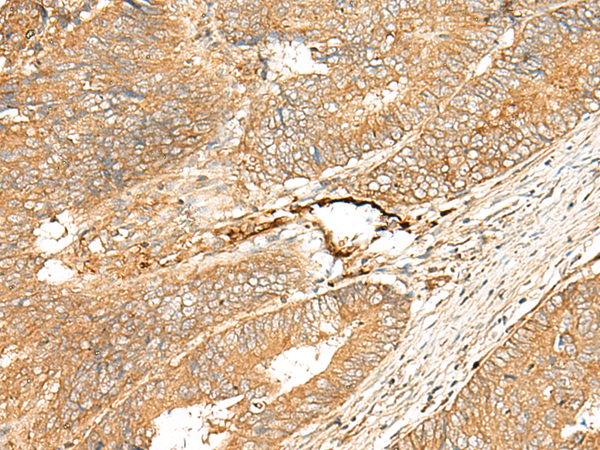

IHC positive control: |

Human colorectal cancer |

IHC Recommend dilution: |

40-200 |